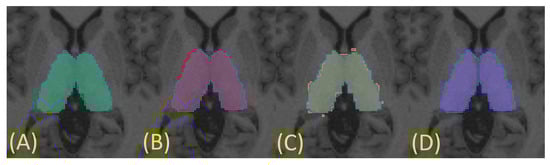

Figure 6.

Axial view of the thalamic masks generated by different methods overlaid on silver standard (in blue): (A) FSL—green; (B) FreeSurfer—red; (C) QuickNAT—yellow; (D) manual segmentation—purple.